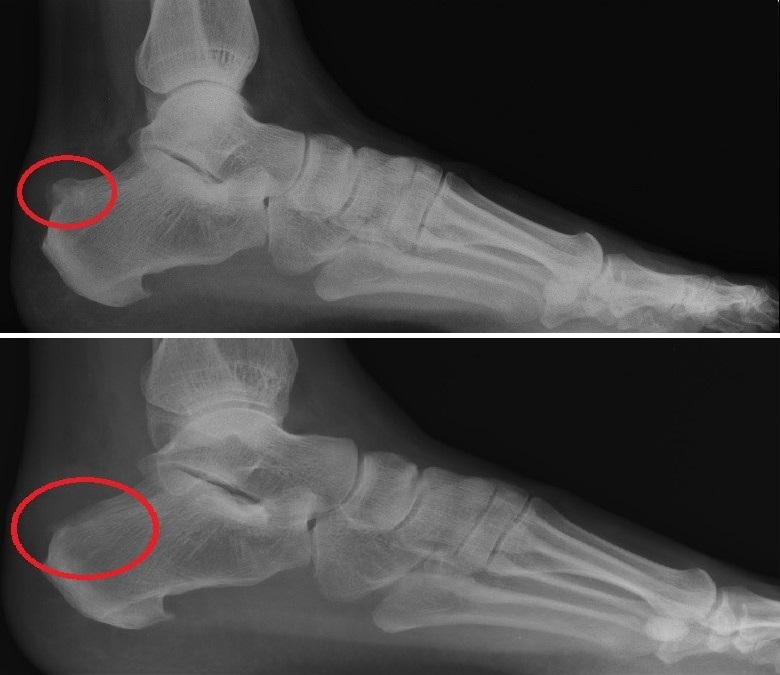

Bij een operatie wordt het verdikte hielbeen afgevlakt, zodat er geen druk meer aanwezig is tegen achillespees en slijmbeurs (Fig 4 -5). Onze chirurgen beheersen zowel de klassieke open ingrepen als de nieuwe minimaal invasieve operaties waarbij via kleine steekgaatjes wordt geopereerd. Zij kunnen met u de beste optie bespreken. De behandeling gebeurt steeds via dagziekenhuis. De voet mag meestal onmiddellijk worden geoefend. Gedurende enkele dagen worden wel krukken gebruikt.

Fig. 4 Fig. 5